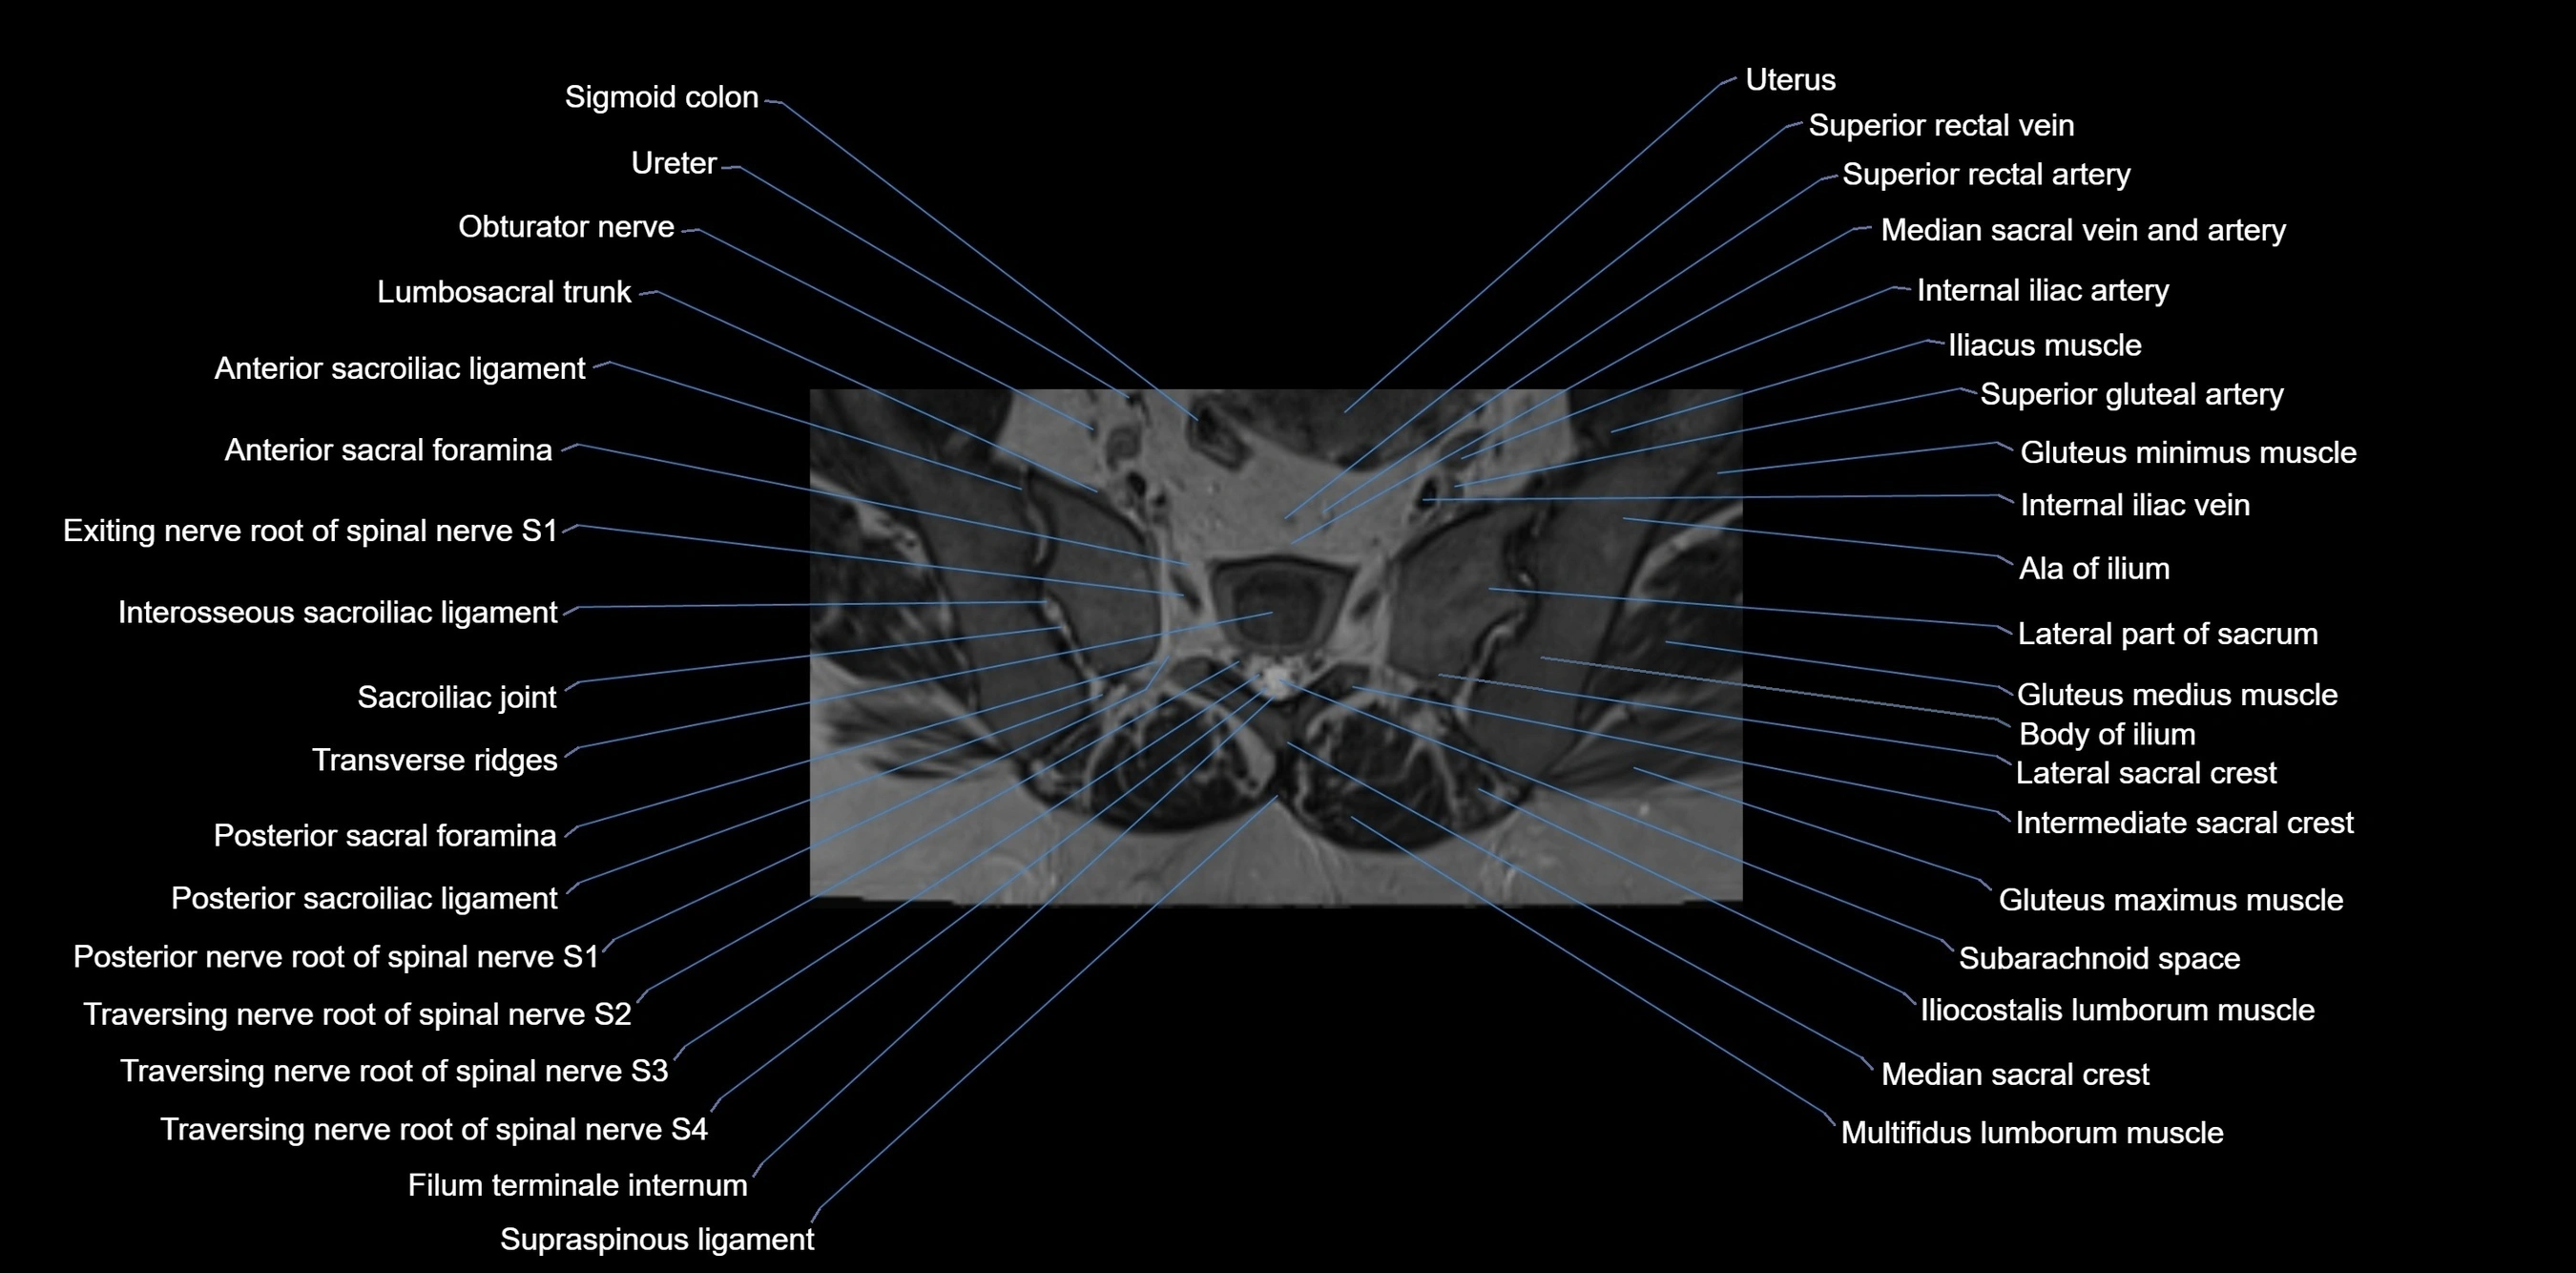

CT VRT image

image